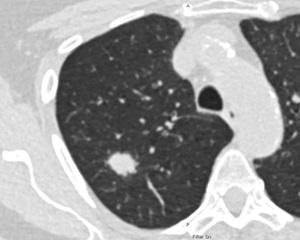

Niedrigdosis-CT der Lunge einer 69-jährigen Raucherin. Die weiße,runde Fläche im Lungengewebe weist auf Lungenkrebs im Frühstadium hin, der in diesem Stadium noch gut behandelbar ist. © Charité/Jens Vogel-Claussen

Die Ergebnisse zeigen: In der PLCOm2012-Gruppe wurden 19,4 Prozent mehr Lungenkrebsfälle gefunden als in der NELSON-Gruppe. Allerdings erfüllten rund sechs Prozent mehr Personen die PLCOm2012-Kriterien. Es erhielten also mehr Menschen eine Strahlendosis – was in die Risikobetrachtung und den Vergleich einfließen muss. „Wenn wir den umfassenderen PLCOm2012-Score mit einem definierten Schwellenwert zugrunde legen, müssen wir zwar etwa sechs Prozent mehr Personen screenen, entdecken aber deutlich mehr Lungenkrebsfälle“, erläutert Professor Martin Reck, Chefarzt des Onkologischen Schwerpunkts an der LungenClinic Grosshansdorf und Letztautor der Studie.